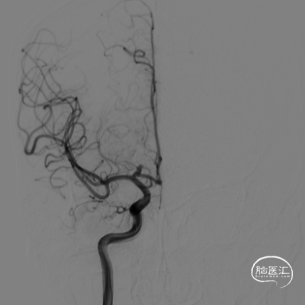

气管插管全麻后全脑血管造影示:

右侧颈内动脉-前交通起始段动脉瘤,动脉瘤大小约3.8*2.5mm,瘤颈约1.0mm,动脉瘤起源于右侧大脑前A1段后壁,朝向后内上,考虑为责任动脉瘤,根据动脉瘤大小、形态等,拟行单纯弹簧圈栓塞治疗。

动脉瘤虽然比较小,但是由于瘤颈只有1mm,动脉瘤又起源于前动脉A1段后壁,使瘤颈开口与颈内动脉之间形成一个较大的锐角弯,因此微导丝超选困难,弹簧圈微导管置入后稳定困难,经反复尝试,最终完全栓塞。